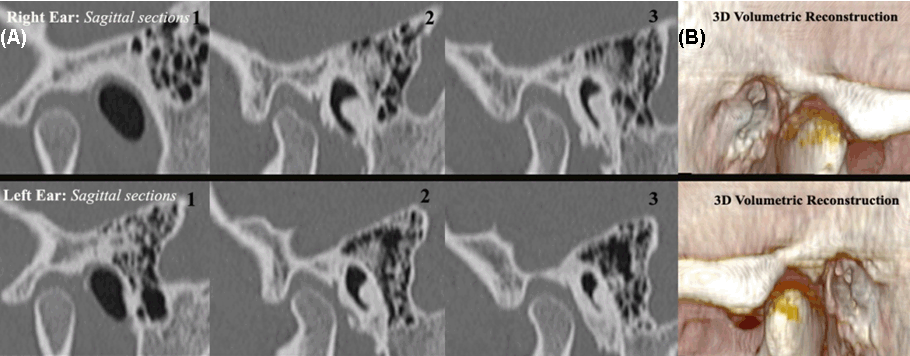

Following findings were noted on HRCT. Broad-based osseous overgrowth of external auditory canal bilaterally, were noted on axial CT images. (Figure 1). Sagittal CT images showed evidence of dense bony protuberances arising from the tympanic and the petrous bone into the external auditory canal space. This resulted in significant narrowing of the ear canal and thus conductive hearing loss bilaterally (Figure 2). On obtaining a detailed history, it was noted that the patient was a frequent swimmer. Thus, the diagnosis of surfer's ear was made. The patient was referred for surgical management of the exostoses.

Figure 2: (A) High resolution computed tomography image showing multiple sagittal sections through the external auditory canals showing bony outgrowth, (B) 3D volumetric reconstruction.